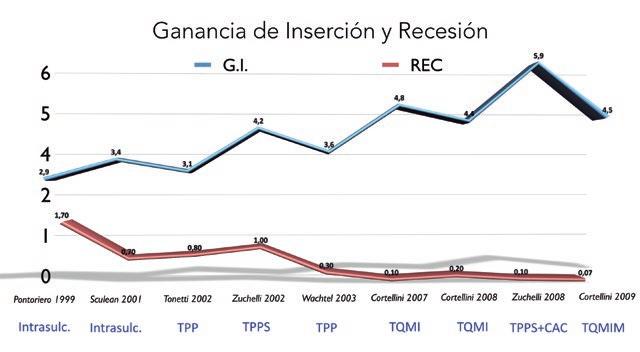

Con el paso de los años se han ido publicando técnicas cada vez más sofisticadas con la intención de conseguir, por un lado, mayor ganancia de inserción y, por otro lado, menor recesión. El cierre primario de la herida resulta muy importante si nuestra intención es conseguir el mejor resultado posible. Pero eso no quiere decir que no se pueda conseguir regeneración periodontal con una técnica muy sencilla como es la intrasulcular. En el gráfico 2 se ven representados alguno de los estudios publicados en la literatura con diferentes técnicas. Se puede apreciar cómo, con la evolución de las técnicas, la ganancia de inserción va mejorando y la recesión va disminuyendo12,13,19,29-34 .

SGRÁFICO 2